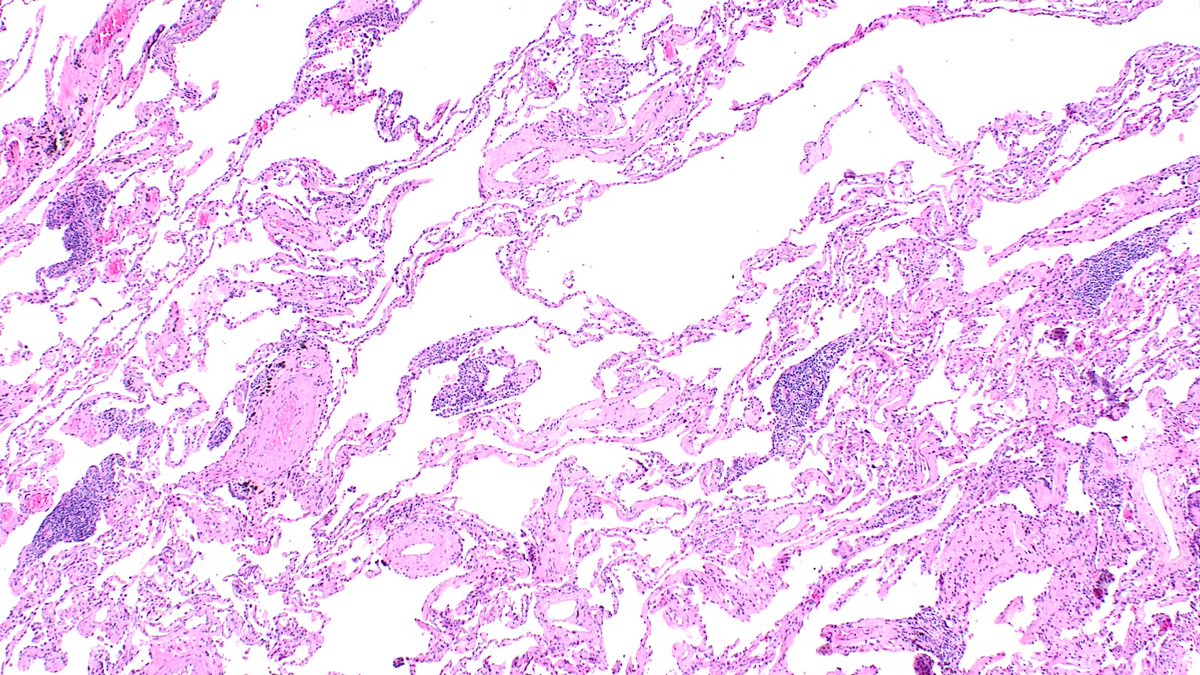

What to do with ill-formed interstitial granulomas on lung resections for malignancy? When are interstitial mononuclear inflammatory cells too numerous? (Same case, away from tumor) #moffitt #moffittpath #lungpath #moffittpathology